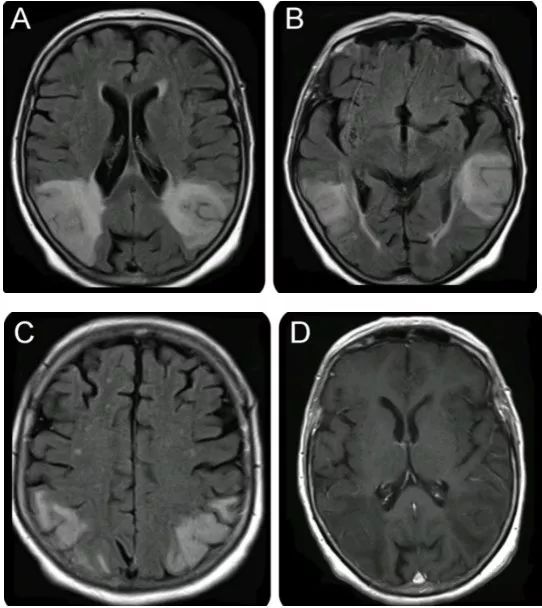

病例8(病例提供: 王浩玥 老师)

患者,女,43岁,因“头晕、行走不稳1月,加重伴左侧肢体无力10天”入院,1月前以“颅内感染、自身免疫性脑炎”收治。激素治疗效果欠佳。1月前增强:

此次复查平扫+强化:

答案:弥漫性大B细胞淋巴瘤

影像表现为:T2/FLAIR显示深部脑白质、皮层、基底节多灶性高信号。常见弥散受限,T2* GRE可见血液产物的“开花征”。T1WC C+多变,通常可见线样和斑片状强化,也可成环形、脑沟样等。脑膜和/或硬脑膜增强。有时类似于血管炎。